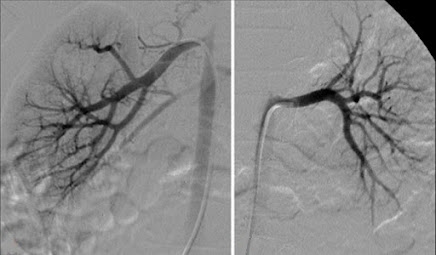

Figura 1.

Angiografía renal derecha e izquierda

Nota: Angiografía renal derecha e izquierda,

se ha inyectado medio de contrate, no se ha empleado la técnica de sustracción

digital, se observa aun tejido graso, aire y los cuerpos vertebrales. Tomada de

Angiografía renal [fotografía]

Figura 2.

Nota: Angiografía renal derecha e

izquierda, se ha inyectado medio de contrate, se emplea técnica de sustracción

digital, se eliminado el tejido grado, aire y óseo, se observa adecuadamente

las estructuras vasculares de cada riñón. Tomada de